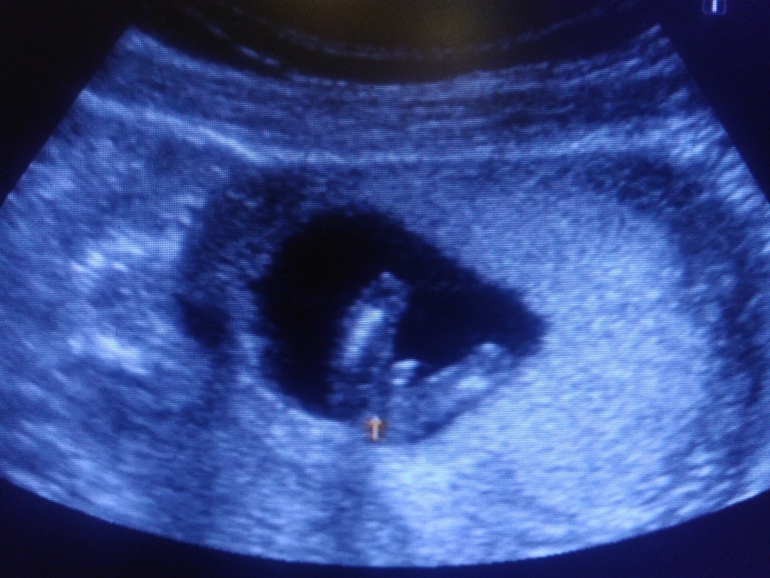

А вот и папина гордость

Активный такой мальчуган, еле рассмотрели все! Сказала врач, что редко такое бывает в 12 недель, но "причандал" серьезный, сказала, что сомнений нет-пацан, и показала со всех сторон папину радость))) лежит на спине, пинается ногами и сосёт палец.